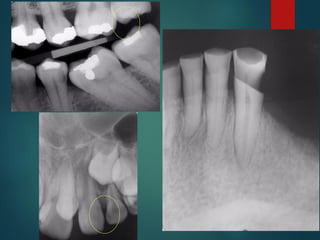

Clasificación

Radiográfica De las

Caries

 Incipiente de esmalte

 De esmalte

 Dentinaria superficial

 Dentinaria profunda

 Sobreproyectada en cámara pulpar

 Penetrante

Clasificación Radiográfica

De Las Caries